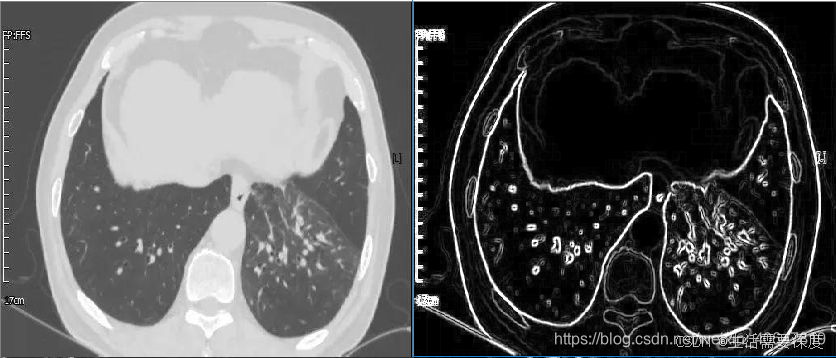

效果